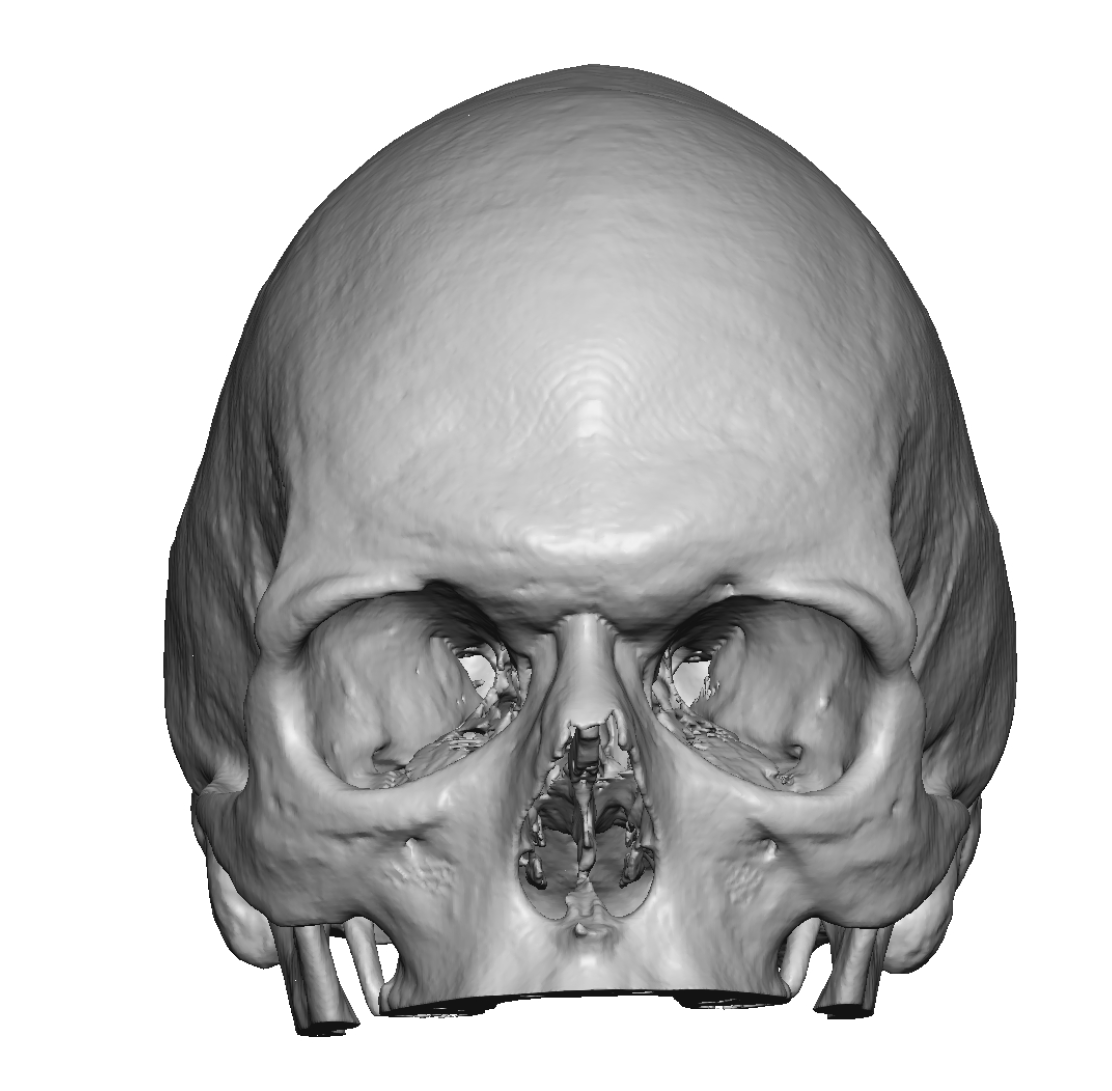

Patient 28

Desire for rounder shape to the top of the head from a congenital parasagittal deficiency skull shape.

Custom skull implant designed to fill in the parasagittal deficiencies.

Desire for rounder shape to the top of the head from a congenital parasagittal deficiency skull shape.

Custom skull implant designed to fill in the parasagittal deficiencies.